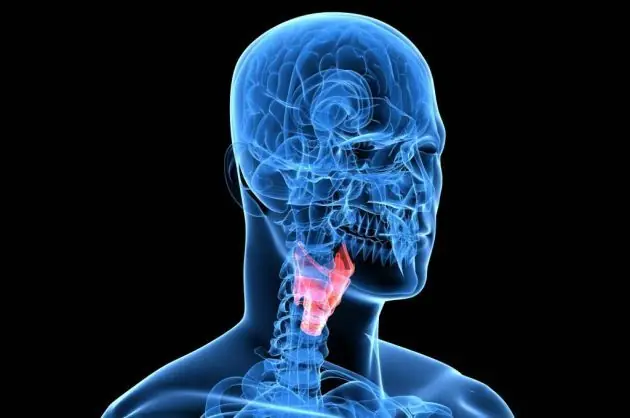

5. Hueso hioides

Con forma de herradura, este hueso tiene la particularidad de ser el único que no se conecta con otro hueso. El hueso Hioides está en la garganta, entre el mentón y el cartílago de la tiroides. La función del hueso hioides es trabajar con la laringe y lengua, dando la base para producir los sonidos vocales.